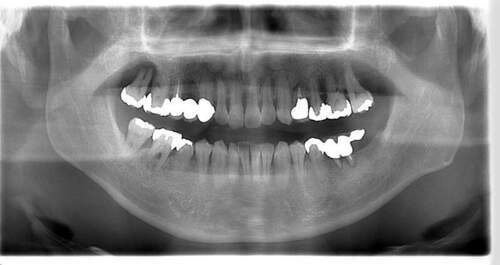

インプラント治療の症例5

レントゲン写真

- Before

- After

| 年齢 | 60代・女性 |

| 主訴 | 左下6番、7番 歯ぐきの腫れが気になり来院。 歯周病がかなり進行しており骨がほとんどない状態で動揺もあった。 |

| 治療内容 | インプラント治療 動揺がひどく歯を残すことが難しいため抜歯へ。 その後骨造成を行いインプラントを埋入。 |

| 治療費 | 合計:1,683,000円 内訳 診断料:55,000円 埋入料:165,000円×2本 チタンメッシュ:55,000円×2本 GBR:110,000円×2本 サージカルガイド:66,000円 静脈内鎮静麻酔:77,000円×2回 2次オペ:22,000円×2本 仮歯:55,000円×2本 上部構造(フルジルコニア):187,000円×2本 APF(歯肉弁根尖側移動術):110,000円×2本 (2024年1月現在) |

| 治療期間 | 16ヶ月 |

| 治療方針 | 歯周病がかなり進行していて骨吸収がみられるのでチタンメッシュと骨補填材を使った骨造成が必要。 先に骨造成を行い骨が再生されるのを待って埋入手術を行う。 歯ブラシがしやすくなるようにAPF ( 歯肉弁根尖側移動術 )も行う。 |

| 特記事項 | 今回は印象材ではなく光学スキャナーを使用して型どりを行った。 |

| 担当者所見 | 骨が再生するか難しいところだったが無事埋入でき問題なく結合できた。 また今回は印象材ではなく光学スキャナーを使用して印象したため患者さまの負担がかなり軽減されたと思う。 上部構造セット後しっかりとかめている。 今後も定期的にメインテナンスしていく。 |